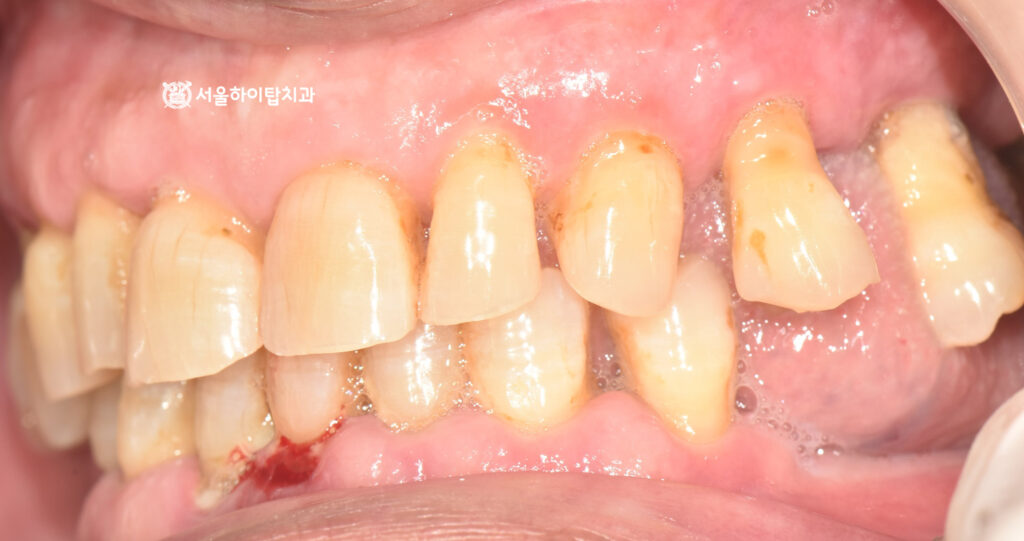

입을 다물었을 때 보는

측면, 정면 사진에서도

정출되어 치근이 보이는 모습과

출혈, 잇몸 부종, 전치부 마모 등

전형적인 심한 치주염의 양상을

보여주고 있습니다.

빠른 치료가 요구되는 상황입니다.